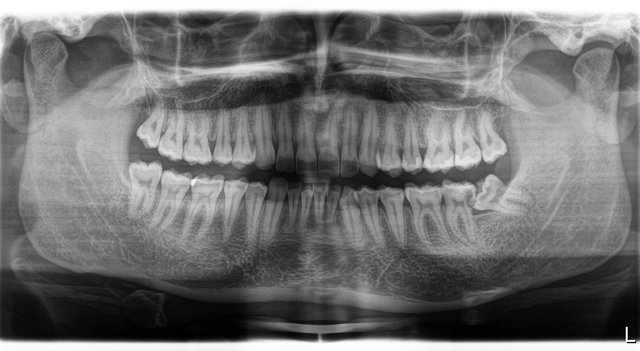

Verlagerung der Weisheitszähne

Follikuläre Zysten um die unteren beiden Weisheitszähne